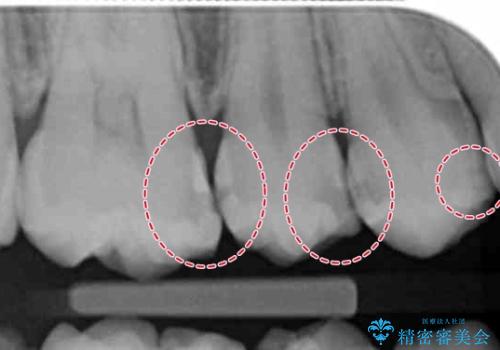

- 昔つめた材料が欠けたこと、歯の捻転を主訴に来院されました。

矯正治療の希望はなかったため、被せ物で歯の形を修正することになりました。

不適合だった詰め物の裏側に大きな虫歯がありました。

セラミックインレーやアンレーでは強度に不安が残るため、クラウンでの修復処置としました。